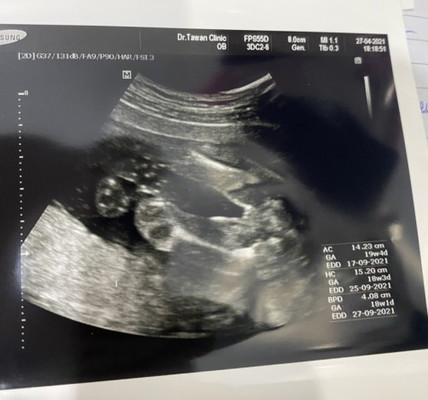

แบบนี้ได้ผู้หญิงชัวร์ไหมค่ะ

คนแรกได้ผู้ชายค่ะ คนนี้เลยอยากได้ลูกสาว คุณหมอบอกผู้หญิง แต่ดูไม่เป็นเลยจ้า

มีกลีบๆผู้หญิงจ้า